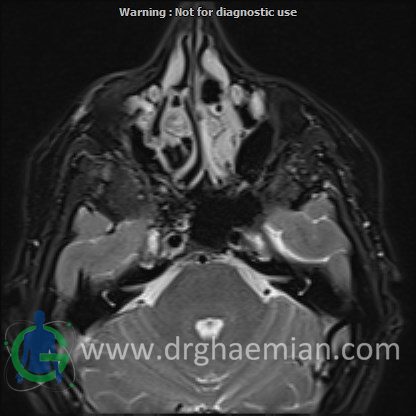

ام آر آی اوربیت با استفاده از آهنربا و امواج رادیویی تصاویری از اوربیت ها، اعصاب، عضلات و بافت های اطراف آن ایجاد می کند. در این کیس مننژیوم مغزی در پشت چشم بیمار دیده میشود.

Technique : Axial T1 , Axial , sagittal , coronal FSE T2 , coronal T1, sagittal fat sat T2 , Axial , sagittal T1 post Gd .

thickening of posterolateral of right orbit wall ( low T1/T2/STIR ) with mass effect on right temporal pole & right orbital content/proptosis , with adjacent dural thickening & post contrast enhancement ( 33x41mm – without significant change to prior MRI – 1403/09/20) suggestive for :

1.meningioma

2.fibrosis plasia with dural thickening & less probably sclerotic bone metastasis